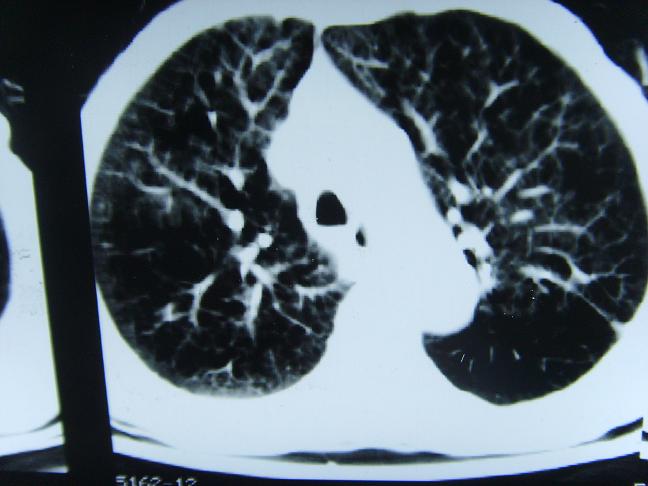

考虑  右肺新生物伴右下肺阻塞性肺炎,肺不张.右侧胸腔积液

考虑:右侧中心型肺癌伴下肺肺不张。

1)右肺中央型肺癌伴右肺下叶肺不张。2)慢性支气管炎,肺气肿。3)右侧胸腔积液。

1)右肺中央型肺癌伴右肺下叶肺不张。2)慢性支气管炎,肺气肿。3)右侧胸腔积液

右肺中央型肺癌伴右肺下叶肺不张。慢支肺气肿。右侧胸腔积液。